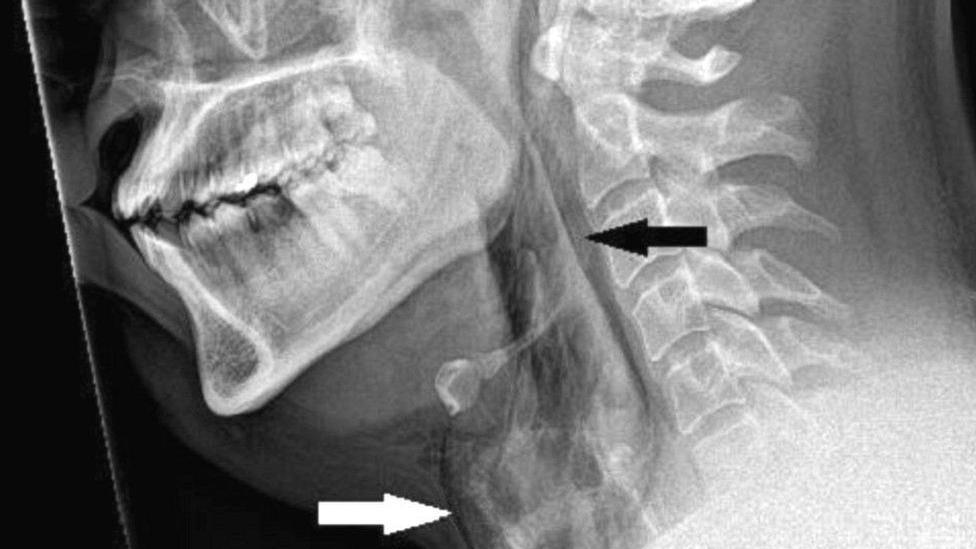

Un equipo médico emitió una advertencia después de que un hombre se perforara la garganta cuando intentó detener un estornudo.

El paciente, de unos 30 años, fue trasladado al hospital Ninewells, en Dundee, Inglaterra, con fuertes dolores, después de haberse apretado la nariz y cerrado la boca para reprimir el estornudo.

Las exploraciones revelaron que sufrió un desgarro de 2 mm en la tráquea.

Cuando los médicos examinaron al paciente, escucharon un crujido al tocarle el cuello y descubrieron que no tenía control de movimiento.